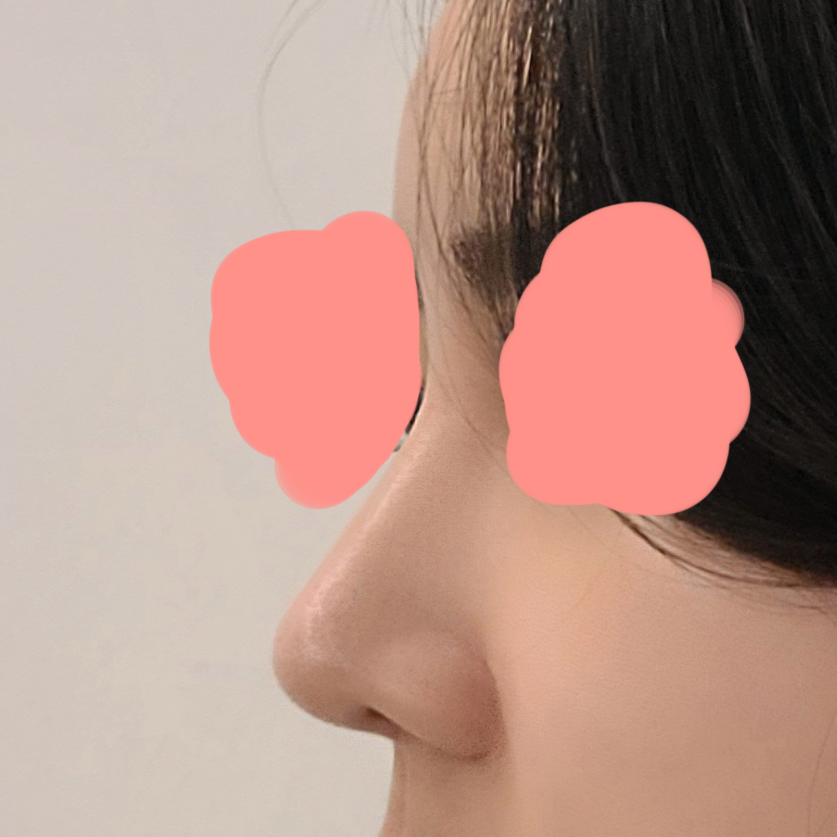

코성형 1개월차 찐 후기:)

NAME : 배세란

2022.08.24